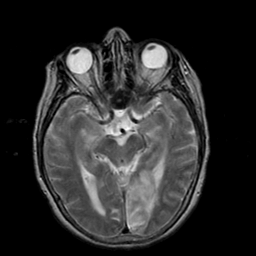

Stroke:T2-weighted MR #2 -- Slice #10

[Home][Help][Clinical] Slice 10